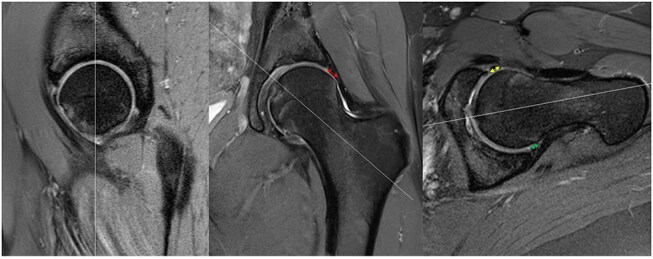

术前x线测量可以帮助预测髋关节唇裂患者最终接受修复还是初级重建。本研究调查了影像学参数是否:(i)术前预测唇部修复与重建,(ii)与唇部T2磁共振成像(MRI)定位值相关。这项回顾性比较研究包括14-50岁的患者,他们在一个机构接受了2年以上的唇部修复或重建。既往有开放或关节镜髋关节手术或术前CT和MRI成像不充分的患者被排除在外。在术前MRI图像的多个位置测量唇部大小。盲法评价者采用三维CT分析记录外侧中心边缘角(LCEA)、髋臼版本、Tonnis角、髋臼覆盖、α角、股扭转和颈轴角(FNSA)。通过对每位患者的最佳矢状切面进行测序分析,获得唇部的T2 MRI定位值。单变量混合线性模型用于确定每次x线摄影测量与决定修复或重建阴唇之间的关联。包括52例手术。唇部大小对进行唇部重建和修复没有预测作用。接受唇部重建的可能性与LCEA (P = 0.003)和Tonnis角(P = 0.034)相关。(P

Preoperative radiographic measurements may help predict which patients with hip labral tears ultimately undergo repair versus primary reconstruction. This study investigated if radiographic parameters: (i) preoperatively predict labral repair versus reconstruction and (ii) correlate with T2 magnetic resonance imaging (MRI) mapping values of the labrum. This retrospective comparative study included patients aged 14-50 years who underwent labral repair or reconstruction at a single institution over a 2-year period. Patients with prior open or arthroscopic hip surgery or who had inadequate preoperative computed tomography (CT) and MRI imaging were excluded. Labral size was measured at multiple positions on preoperative MRI images. A blinded reviewer used three-dimensional CT analysis to record lateral center edge angle (LCEA), acetabular version, Tonnis angle, acetabular coverage, alpha angle, femoral torsion, and neck-shaft angle (FNSA). T2 MRI mapping values of the labrum were obtained via sequencing analyses on each patient's optimal sagittal cut. Univariate mixed linear models were used to identify associations between each radiographic measurement and decision to repair or reconstruct the labrum. Fifty-two operations were included. Labral size had no predictive effect on undergoing labral reconstruction versus repair. Likelihood for undergoing labral reconstruction was associated with LCEA (P = .003) and Tonnis angle (P = .034). There was an association (P < .05) between labral T2 mapping values and all radiographic parameters except for FNSA and combined version. Labral size was not associated with whether patients underwent labral reconstruction or repair. The data showed an association between labrum T2 mapping values and nearly all radiographic parameters.